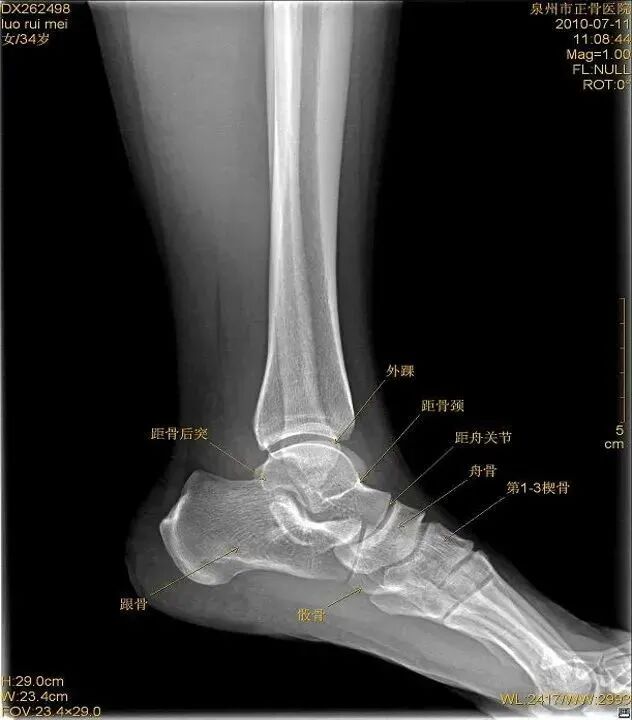

扭伤机制

距骨在踝穴内有无倾斜,会通过影响关节面接触面积而影响关节所受应力的大小。有轻度倾斜,关节面所受到的应力会因为承重面积变小而明显增加。

距骨体前宽后窄,当踝关节背屈时,其宽部进入踝穴,能防止踝关节向后脱位;当跖屈时,其窄部进入踝穴,则关节不稳,易向侧方活动。

旋后扭伤分类

外旋位扭伤受伤时距骨受到外旋外力,或小腿内旋距骨受到相对外旋外力。随着外旋暴力增大下胫腓联合主要韧带断裂,下胫腓联合分离。严重的多合并外踝骨折或内侧韧带断裂。